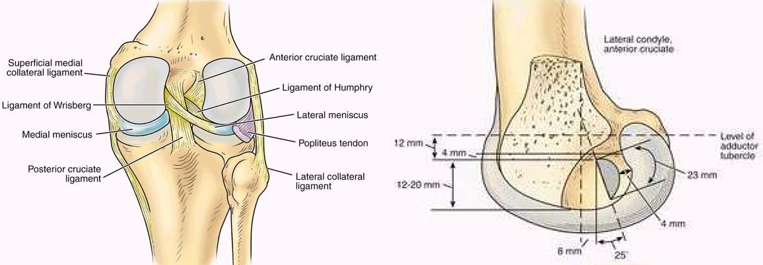

ACL的解剖特点

1、ACL起于胫骨髁间棘前方稍偏内侧,斜向后上止于股骨外髁髁间侧面后部;长约15-20mm(胫骨后推)

2、胫骨端附着部较粗大,呈卵圆形,面积约3平方厘米。

3、股骨附着部相对细小,呈扇形,面积约2平方厘米。

ACL三束:前内束屈膝时紧张;后外束伸膝时紧张;中间束在膝关节屈伸运动中始终保持张力。

正常ACL与胫骨平台保持一定的角度,屈膝90度时约30度,伸直时为40~45度。

前交叉韧带双股重建

解剖基础

胎儿膝关节显示:两个功能束(AM,PL)

伸直时AM,PL的股骨点垂直排列,两束平行。

屈曲90°时,AM,PL的股骨点平行,两束交叉

膝关节屈曲90 °时PL松弛,而伸直时PL紧张状态